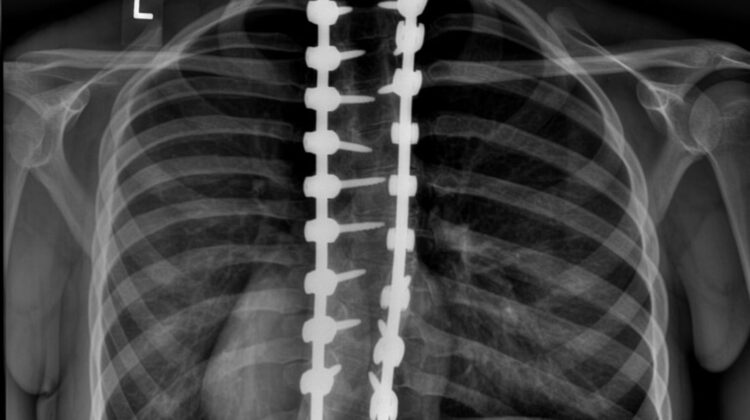

زاوية كوب هي المقياس الطبي المستخدم لتحديد درجة انحناء العمود الفقري في الأشعة السينية.

ويتم حسابها من خلال قياس ميل الفقرات الأكثر انحناءً.

وتتم غالبًا باستخدام قضبان ومسامير طبية تساعد على تثبيت العمود الفقري في الوضع الصحيح.